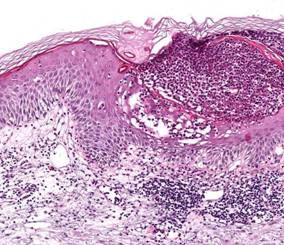

AbstractAcute generalized exanthematous pustulosis (AGEP) is an uncommon acute pustular eruption most often triggered by systemic drugs. We report a 68-years-old female patient who developed AGEP after the intake of fenofibrate. To our knowledge, this is the first report of this association in medical literature. Therefore, fenofibrate should be added to the list of AGEP-causing agents. IntroductionIn 1980 Beylot et al. [1] introduced the term pustuloses exanthemátiques aiguës généralisées (acute generalized exanthematous pustulosis [AGEP] in English medical literature) to rename the condition formerly termed exanthematic pustular psoriasis by Baker and Ryan in 1968 [2], to describe a subgroup of patients with pustular psoriasis who had a very acute pustular eruption, drug intake and no history of psoriasis. Fenofibrate is a lipid regulating agent of the fibrate class approved as an adjunct to diet in the treatment of adult patients with primary hypercholesterolemia, mixed dyslipidemia and hypertriglyceridemia [3,4,5]. Recent data also indicate its utility for optimizing reduction in the risk of cardiovascular disease in patients with type 2 diabetes and metabolic syndrome, as well as delaying the progression of diabetes-related microvascular complications, when combined with a statin [4]. Cutaneous adverse reactions (CAR) attributed to fenofibrate are rare and include acute hypersensitivity reactions such as severe skin rashes, urticaria, photosensitivity reactions, contact dermatitis, Stevens-Johnson syndrome, toxic epidermal necrolysis, pruritus, alopecia, herpes zoster, herpes simplex, acne, sweating, nail disorder and skin ulcer [3,5,6]. AGEP had never been associated with fenofibrate therapy. Case ReportA 68-year-old woman with atrial fibrillation, arterial hypertension and diabetes mellitus was taking acenocoumarol (dose based on International Normalized Ratio (INR) values), digoxin 0.2 mg/day, amlodipine 5 mg/day and rosiglitazone/metformin 2 mg/1000 mg once/day for several years. Three weeks before admission the patient was diagnosed with hypertrigliceridemia and was prescribed fenofibrate 267 mg/day. After 7 days of treatment, she developed an erythematous pustular eruption on inframammary folds, axillae, inner surface of both arms and laterothoracic areas associated with subfebrile temperatures. She attended her local doctor and was suspected to have scarlet fever, being medicated with intramuscular penicillin. Because no clinical improvement was achieved and the rash continued to spread, she returned to her doctor 2 days later and was advised to cease penicillin, was medicated with intravenous bolus of corticosteroid for suspicion of drug-induced cutaneous reaction, and was referred for a dermatological opinion concerning diagnosis and treatment. On physical examination, we observed widespread edematous erythema over the trunk, arms, buttocks, thighs and intertriginous areas, accompanied by many small, nonfollicular, superficial pustules. On the neck, axillae and inframammary folds confluence of pustules produced lakes of pus (Fig. 1). The mucous membranes, palms, and soles were unaffected. She was febrile (38.2 oC) and referred malaise and asthenia. She denied previous therapy with fenofibrate and reported no adverse reaction to other drugs. Personal or family history for psoriasis was negative. Routine blood tests revealed leukocytosis (12400/mm3; normal: 4000-11000/mm3) with neutrophilia (10400/mm3; normal: 2500-7500/mm3) and raised C-reactive protein (16.6 mg/L; normal < 5.0 mg/L). The remaining blood panel, urinalysis and cultures obtained from blood samples and pustular swabs were normal or negative. The skin biopsy specimen demonstrated non-follicular intra- and subcorneal pustules containing neutrophils, spongiosis, mild edema of the papillary dermis and perivascular inflammatory infiltrate mainly composed of neutrophils and eosinophils (Fig. 2). The histological findings were consistent with the clinical diagnosis of AGEP. Management involved withdrawal of fenofibrate, introduction of oral prednisolone (30 mg/day with a 2-weeks tapering), bathing with antiseptic solution (potassium permanganate) and emollients, which resulted in resolution of the exanthema within 1 week, followed by thin desquamation. For lipid control, the patient was prescribed simvastatin 20 mg/day. About 2 months after the resolution of the dermatosis, skin patch tests were performed with the Portuguese Contact Dermatitis Group standard series and fenofibrate capsules (267 mg) at 1, 5 and 10% in petrolatum. The tests were read at 48 and 96h and scored according to the International Contact Dermatitis Research Group grading scale. Only positivity for potassium dichromate (+) was detected. After a 6-month follow-up period there was no recurrence of the skin lesions. DiscussionThe estimated incidence of AGEP is approximately 1 to 5 cases per million per year [7,9]. More than 90% of cases of AGEP are drug induced, particularly by antibiotics and mainly beta-lactams and macrolids [7,8]. Few cases are related to other causative factors such as viral infections, mercurial antiseptics, topical agents, pneumococcal vaccine, herbal medications, foods, ultraviolet light exposure and spider bite [7,8]. Bernard et al. [9] demonstrated a high frequency of HLA-B51, -DR11 and -DQ3 in patients with AGEP. The interval between the administration of the drug and the onset of the eruption is usually 2 or 3 days for antibiotics and longer (3-18 days) for drugs other than antibiotics. Our patient started fenofibrate 7 days before the eruption. The diagnostic criteria of AGEP, initially proposed by Roujeau et al.[8] include: (i) numerous, small, non-follicular and sterile pustules arising on a widespread edematous erythema, with burning and/or itching; (ii) fever exceeding 38oC; (iii) histopathologic findings of subcorneal and, sometimes intraepithelial spongiform pustules; (iv) blood neutrophil count above 7000/mm3; and (v) acute course with spontaneous resolution of the pustular eruption in less than 15 days, followed by a characteristic postpustular pin-point desquamation. Recently, a validation score based on morphologic and histologic criteria, and disease course was elaborated by the EuroSCAR study group [7]. Our patient had a classic drug-induced AGEP with typical morphology, course and histology, fulfilling the diagnostic criteria established by Roujeau et al. [8]. Besides, according to the criteria of the EuroSCAR study group, fenofibrate-induced AGEP was considered a definite diagnosis (12 points; range for definite AGEP, 8-12). Lymphocyte transformation tests and skin patch tests (SPT) can be useful for diagnostic confirmation, and positive results suggest involvement of T cells in AGEP [10]. The percentage of positive SPT to the culprit drugs is frequently high (up to 80%) in patients with AGEP, particularly for antibiotics [11]. However, negative tests do not exclude this diagnosis. Early diagnosis of AGEP and the differentiation from other dermatoses, such as generalized pustular psoriasis (von Zumbusch type), subcorneal pustular dermatosis (Sneddon-Wilkinson disease), hypersensitivity syndrome with pustulation, pustular vasculitis or even toxic epidermal necrolysis [7,8], are important to avoid unnecessary and potentially dangerous drug therapy. Additionally, as occurred in our patient, the combination of fever, leucocytosis and pustules is often misdiagnosed as acute infectious disease leading to unnecessary administration of antibiotics. The withdrawal of the responsible drug is the main treatment for AGEP, in combination with topical corticosteroids and antipyretics [1,7]. Because lipid lowering is effective for primary and secondary prevention of cardiac events, one might expect an increase in the use of the various lipid-lowering agents including fenofibrate and, as a result, the associated CAR. To our best knowledge there are no previous reports in the international medical literature of AGEP induced by the ingestion of fenofibrate. Therefore, this drug should be added to the list of potential causes of AGEP. References1. Beylot C, Bioulac P, Doutre MS. Pustuloses exanthématiques aiguës généralisées, à propos de 4 cas. Ann Dermatol Venereol. 1980; 107: 37- 48. PMID: 6989310 2. Baker H, Ryan TJ. Generalized pustular psoriasis: A clinical and epidemiological study of 104 cases. Br J Dermatol. 1968; 80: 771- 793. PMID: 4236712 3. U.S. Food and Drug Administration. Drugs@FDA: Fenofibrate. Available at: http://www.accessdata.fda.gov/scripts/cder/drugsatfda/index.cfm. Accessed August 10, 2008. 4. Zambon A, Cusi K. The role of fenofibrate in clinical practice. Diab Vasc Dis Res. 2007; 4 Suppl 3: S15- 20. PMID: 17935056 5. Balfour JA, McTavish D, Heel RC. Fenofibrate: A review of its pharmacodynamic and pharmacokinetic properties and therapeutic use in dyslipidaemia. Drugs. 1990; 40(2): 260- 290. PMID: 2226216 6. Roberts WC. Safety of fenofibrate: US and worldwide experience. Cardiology. 1989; 76(3): 169- 179. PMID: 2673510 7. Sidoroff A, Halevy S, Bavinck JNB, Vaillant L, Roujeau J-C. Acute generalized exanthematous pustulosis (AGEP): a clinical reaction pattern. J Cutan Pathol. 2001; 28: 113- 119. PMID: 11168761 8. Roujeau JC, Bioulac-Sage P, Bourseau C et al. Acute generalized exanthematous pustulosis: Analysis of 63 cases. Arch Dermatol. 1991; 127(9): 1333- 1338. PMID: 1832534 9. Bernard P, Lizeaux-Parneix V, Miossec V et al. HLA et predisposition génétique dans les pustulosis exanthématiques (PEAG) et les exánthemes maculo-papuleux (EMP). Ann Dermatol Venereol. 1995; 122: S38. 10. Britschgi M, Pichler W. Acute generalized exanthematous pustulosis: a clue to neutrophil-mediated inflammatory processes orchestrated by T cells. Curr Opin Allergy Clin Immunol. 2002; 2(4): 325- 331. PMID: 12130947 11. Wolkenstein P, Chosidow O, Flechet ML et al. Patch testing in severe cutaneous adverse drug reactions, including Stevens-Johnson syndrome and toxic epidermal necrolysis. Contact Dermatitis. 1996; 35: 234- 236. PMID: 8957644 © 2008 Egyptian Dermatology Online Journal |